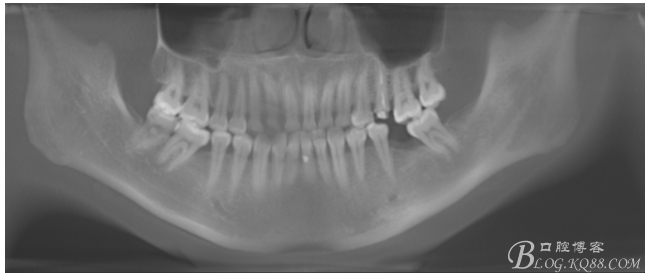

檢查:36.46缺失,36缺牙區(qū)近遠中間隙約3mm,46缺牙區(qū)間隙約0.5mm,37.47.48近中傾斜,48近中面齲壞達牙本質(zhì)淺層,37牙周探診4mm,47近中探診深度5-6mm,不松,口內(nèi)照片及CT片如下:

術(shù)前CT